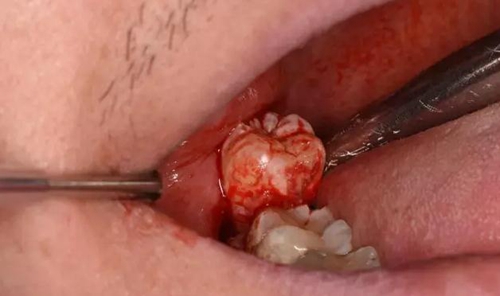

圖12.最后使用挺力和撬力,使48從合向脫位

圖13.刮匙清理牙槽窩內(nèi)的牙囊壁及肉芽組織